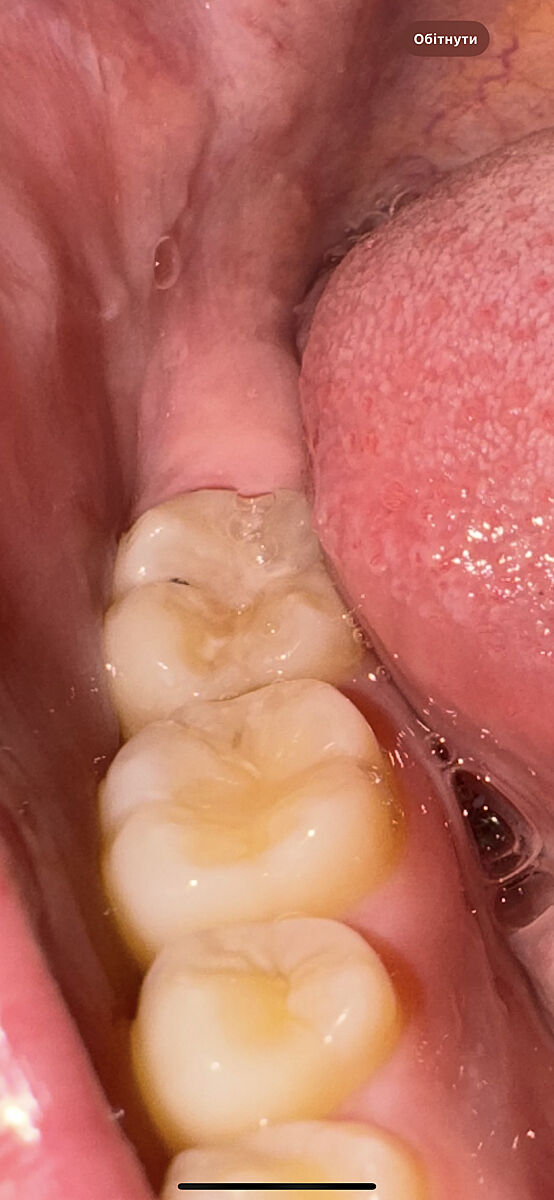

На зубі чорна риска- що це може бути? У дитини на постійному зубі

Це може бути від герметизації зубів?

В стоматолога була в червні, то цієї чорної точки не було

Карієс може починатись